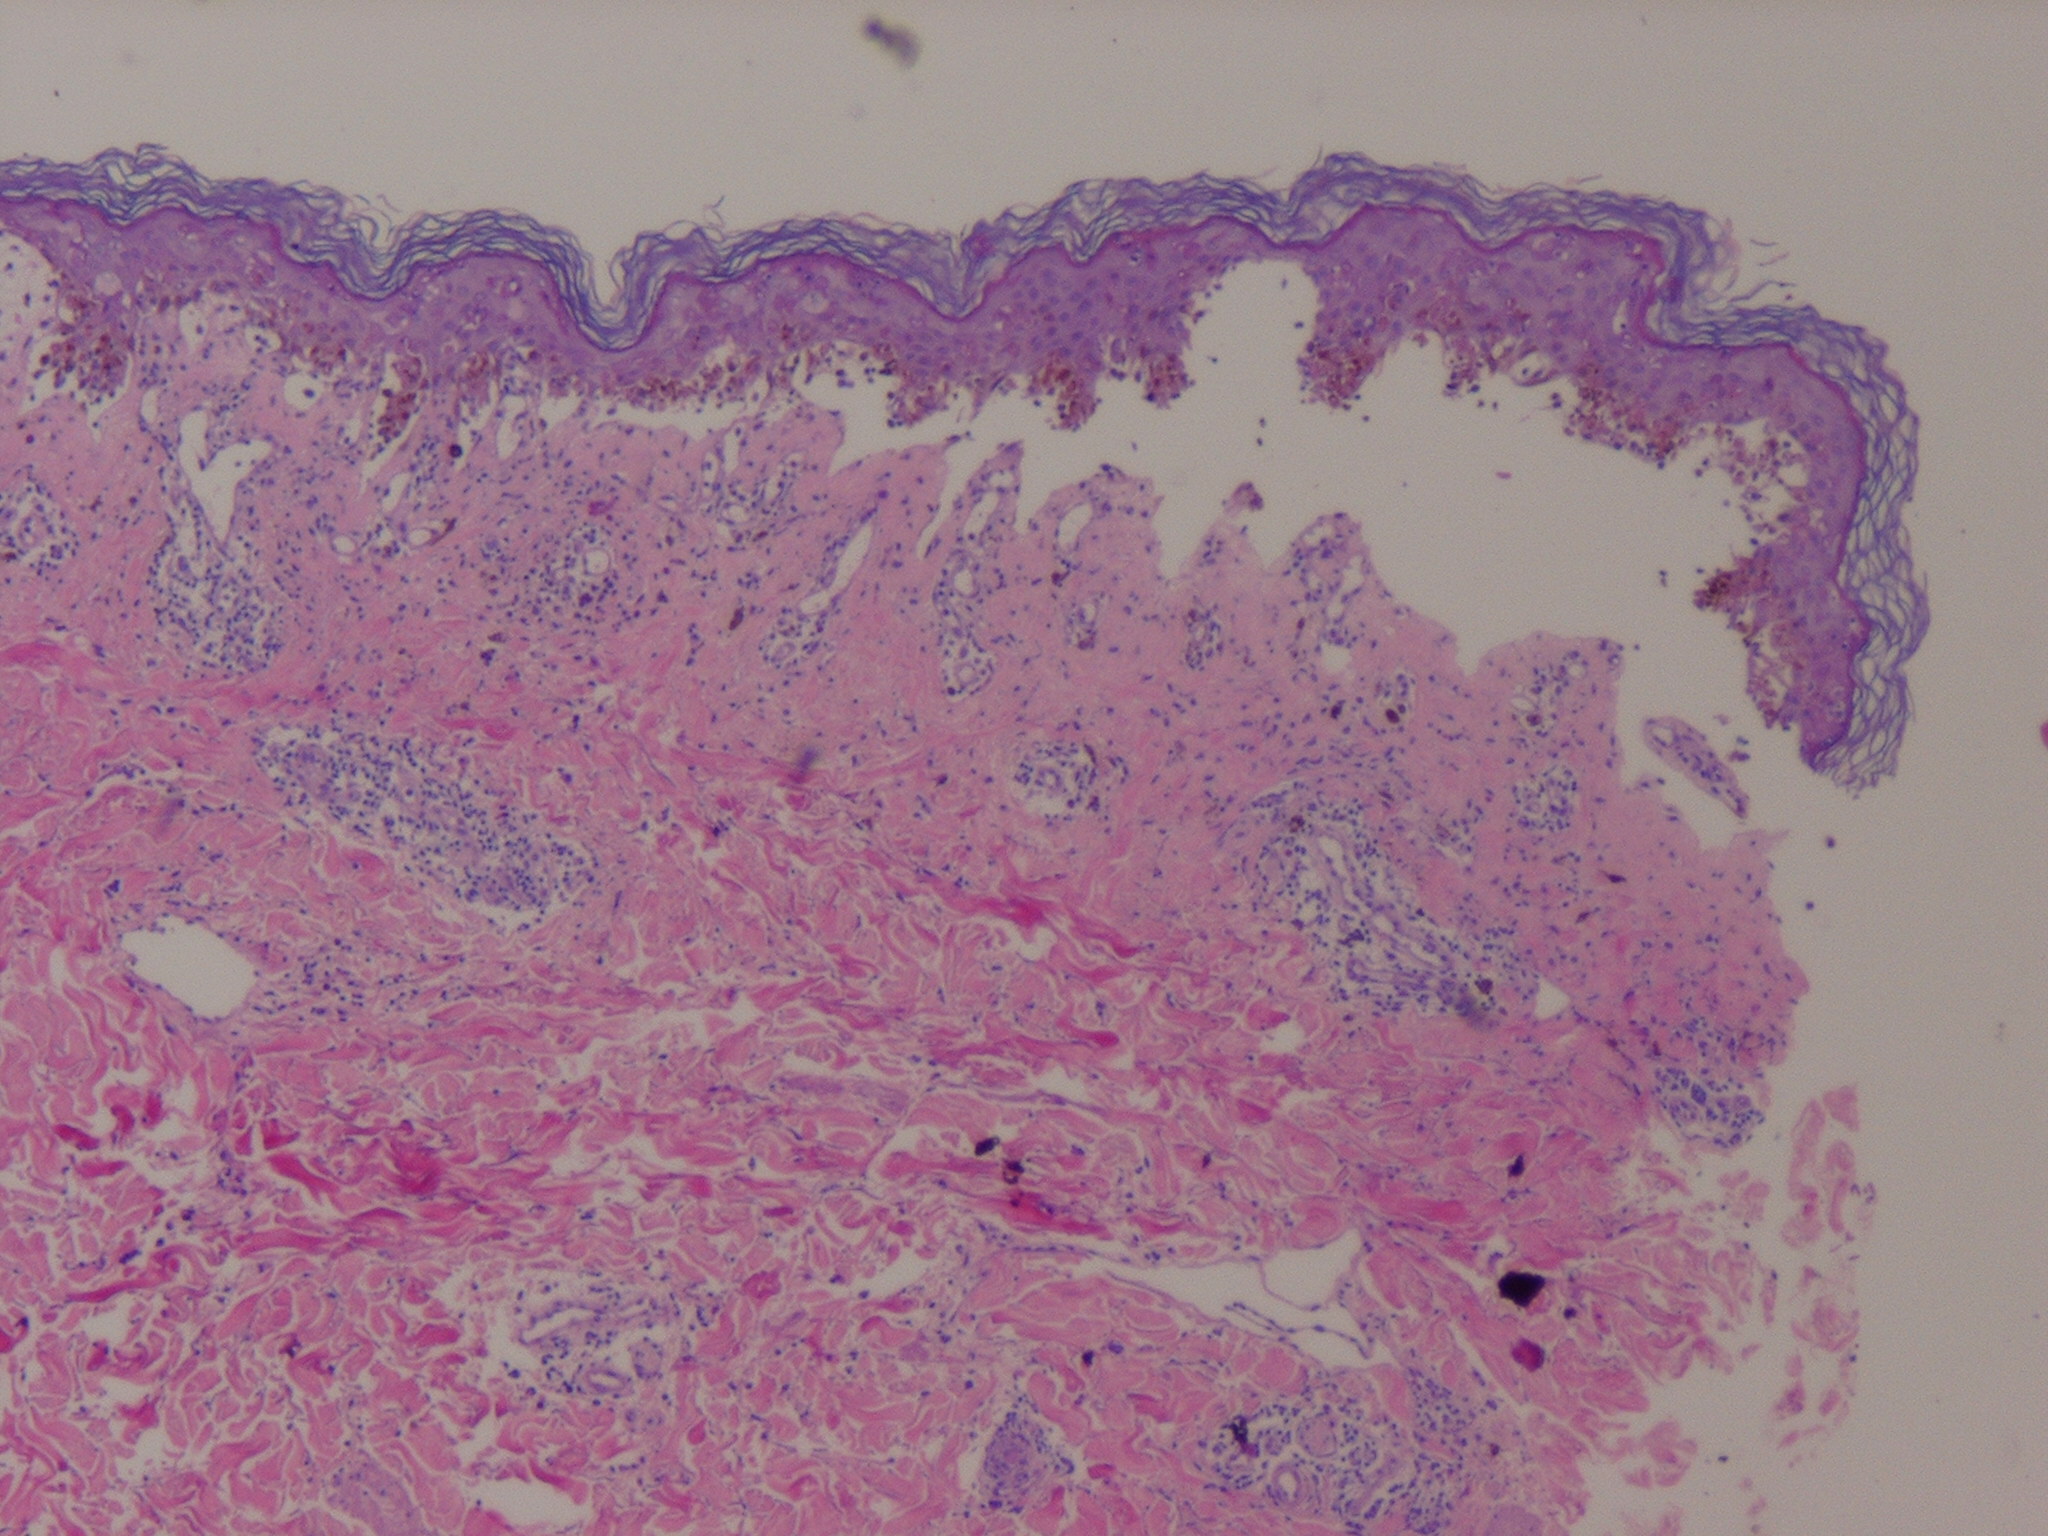

Early lesions of EM exhibit lymphocyte accumulation at the dermal-epidermal interface, with exocytosis into the epidermis, lymphocytes attached to scattered necrotic keratinocytes (satellite cell necrosis), spongiosis, vacuolar degeneration of the basal cell layer, and focal junctional and sub-epidermal cleft formation . The papillary dermis may be edematous but principally contains a dense mononuclear cell infiltrate, which is more abundant in older lesions. The vessels are ectatic with swollen endothelial cells; there may be extravasated erythrocytes and eosinophils. Immunofluorescence findings are negative or non-specific. In advanced lesions sub-epidermal blister formation may occur, but necrosis rarely involves the entire epidermis . In late lesions, melanophages may be prominent.

The histopathologic appearance of EM lesions is different from that of SJS-TEN lesions, in which dermal inflammation is moderate to absent and epidermal necrosis much more pronounced . Still, the histopathologic appearances are somewhat overlapping and do not allow the distinction of EM from SJS-TEN in all instances. The main reason for performing a biopsy is to rule out other diagnoses.